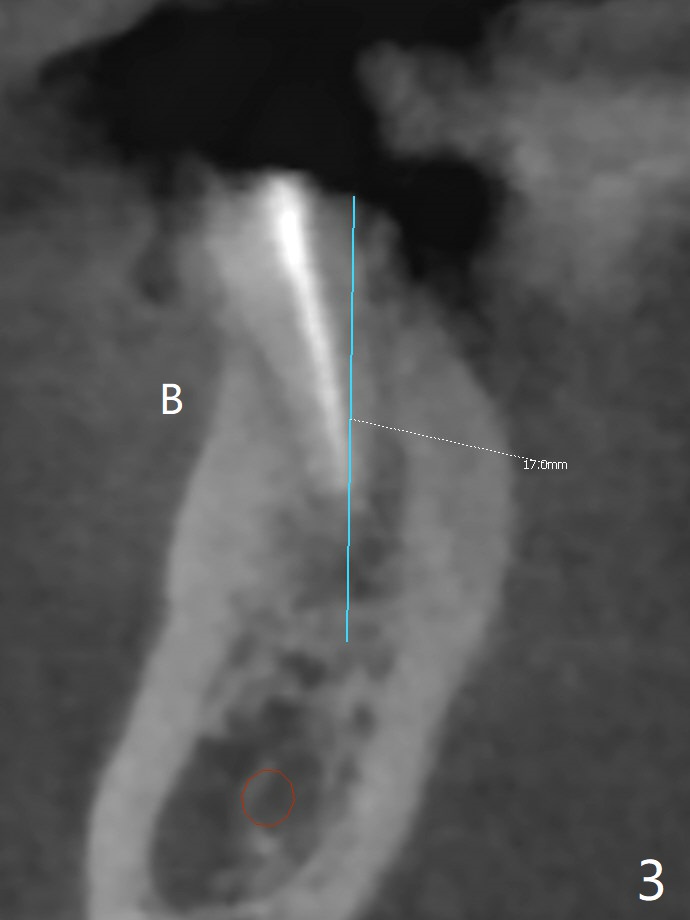

徒手即刻种植缺点是钻洞深度控制不易,尤其是术前设计是骨水平植体,而术中决定使用软组织水平植体。当3毫米reamer达到14毫米深度(骨水平)时,略感到根尖骨质长度。可欣的是4乘17毫米软组织水平植体取得初步稳定性(图二),即刻放置基台(3.5乘5毫米)后,骨粉放入颊侧间隙,有意地把骨粉推向远中(图二:*),好像植体接近颏神经(图二:红色),不过术后没有神经麻木现象,术后分析术前CT表明植体离神经相当远(图三)。术后四个月病人回来做修复,这时我们不关心深部神经了,重点是牙槽嵴周围骨质与植体愈合如何。可以使用sensor 1 (一号传感器,图四:1)和根尖片固定器(黄色,这样减少病人疼痛,恶心,容易放置,拍摄影像好,平行)或者sensor 2(图四:2)加咬翼片固定器(红色,同样容易放置,拍摄影像好,平行,植体螺纹清晰);为了拍摄下颌牙齿多些,传感器放低些(相对于固定器,图四,五),结果得到的信息足够(图六),好像植体已经整合,接着取模。There is no residual cement immediately post cementation with a small escape hole occlusally (Fig.7).